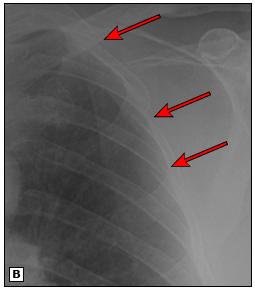

箭头指示的地方就是骨折的位置